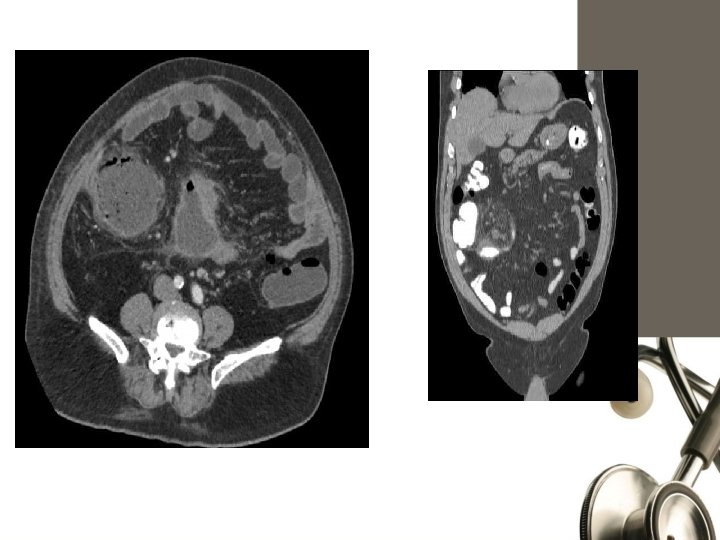

computed tomography (CT) scan - Appendix dilated and the wall is thickened. Periappendiceal phlegmon, and free fluid Periappendiceal fat stranding Thickened mesoappendix Fecaliths but their presence is not pathognomonic of appendicitis.

Ultrasonography. sensitivity of 55% to 96% and a specificity of 85% to 98%. (CT) scan 92% to 97% sensitivity, 85% to 94% specificity

Computed Tomography • Rational use: - Elderly - Atypical presentations - Neoplasms - Acute diverticulits - Intestinal obstruction • MRI: ? ?